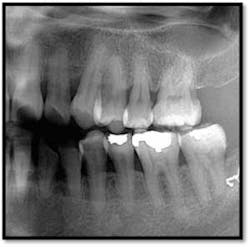

UL/LL reflected in a mirror and UL/LL radiograph

Charting shows that all pockets are now generalized 1-3 mm with no BOP